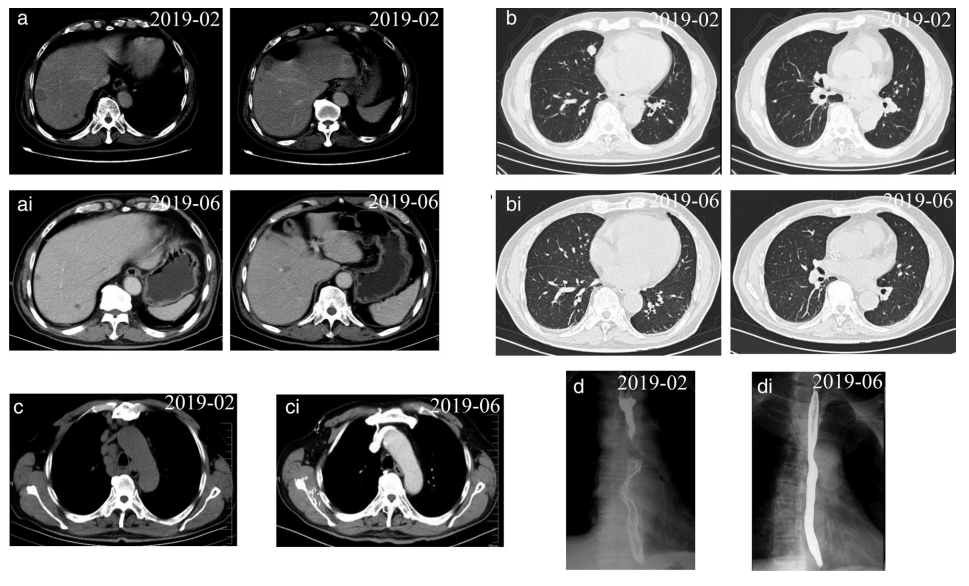

患者男,73,于2019年2月因复发性头痛和胸骨后疼痛入院。胃镜检查显示食管黏膜糜烂和隆起,活检标本病理结果证实小细胞癌诊断。免疫组化(IHC)染色示CK(+)、CgA(−)、Syn(+)、CD56(+)、P40(−)、CD20(−)、CD3(−)、Ki67(80%+)。CT扫描显示肝脏、肺和多个淋巴结转移。诊断结果为食管和贲门的广泛性小细胞癌。

活检样本进行全外显子组测序和IHC分析。MDM2扩增,PD-L1阳性表达(1.83%),肿瘤突变负荷为2.99 Muts/Mb。自2019年2月至7月期间,行6周期特瑞普利单抗(PD-1单抗;D5,240mg)联合依托泊苷(D1~5,100mg)/卡铂(D1,450mg)治疗。

增强CT未见肝脏转移灶明显强化,纵隔4R区淋巴结及肺转移灶完全消失。钡餐造影显示食管壁光滑。复查胃镜示食管病变完全消除,呈瘢痕样改变。患者获得了接近完全缓解(nCR)(图2)。随后给予特瑞普利单抗(D4,240mg)联合依托泊苷(D1~4,100mg)维持治疗。不幸的是,于2019年10月发现颅内转移。因此,立即给予特瑞普利单抗(D2,240mg)加伊立替康(D1,300mg)4周期,并进行1疗程的脑转移放疗。2020年6月,颅内病变达到完全缓解(CR),颅外病变达到nCR。随后给予特瑞普利单抗(240mg)治疗。目前,该患者的总生存(OS)已经超过19个月(图3),目前情况稳定,没有任何严重的不良反应。